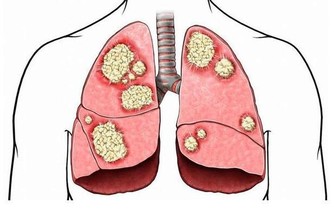

2、子宮肌瘤慢慢萎縮

如今人們對於定期體檢更加重視,很多女性在體檢的時候都檢查出自己患有子宮肌瘤,雖然大多數都是良性的,但也有極少數會存在惡變的可能,嚴重的話還會發展為癌症。

子宮肌瘤主要是由於雌激素過高所導致的,在絕經之後,